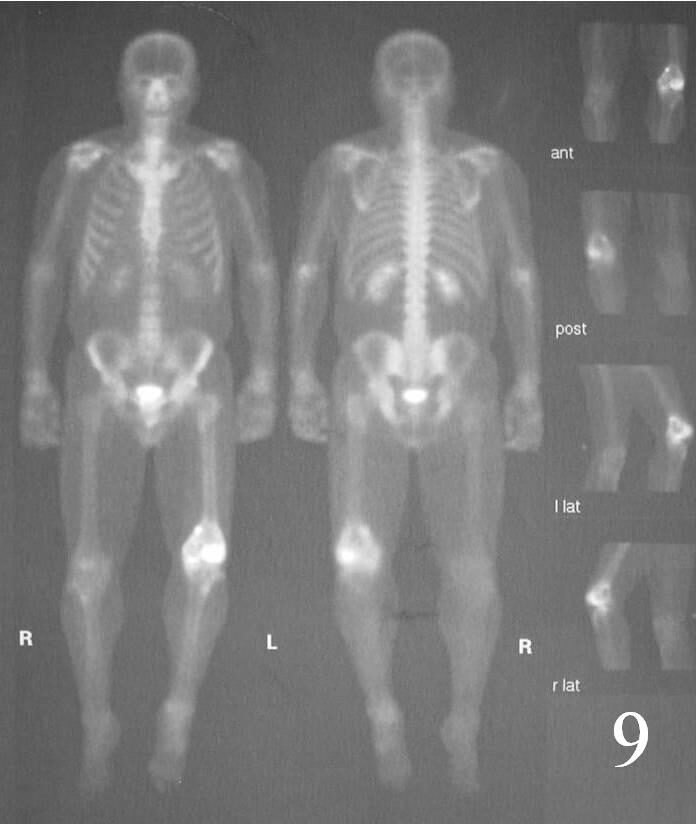

Whole Body Bone Scan

Shows “hot” often with a central “cold” spot in the center of lesion, called “Doughnut Sign” ( Fig. 9)

Fig. 9 Whole body bone scan shows a hot/cold lesion on left knee.